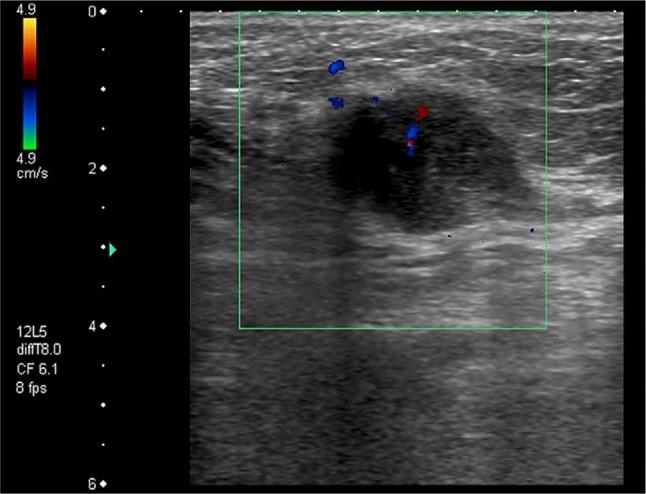

Neoplastic seeding may arise after radiofrequency ablation (RFA) for hepatocellular carcinoma (HCC). A low risk of seeding after RFA (0-1.1%) has been reported, which may rise up to 2.5% if ablation followed diagnostic biopsy. Needle track seeding presents with one or multiple rounded nodules along the needle track located within the peritoneum, along the abdominal muscles, which were penetrated by the needle, pleural surface, or in the subcutaneous and cutaneous tissues. The most widely used method for the assessment of seeding nodules is ultrasound (US), which usually displays hypoechoic nodules with intralesional vascularization. Fine needle aspiration biopsy of the nodule suspicious for malignant implant is mandatory to confirm the diagnosis and plan therapy. Wide surgical excision is the treatment of choice for neoplastic seeding. Thanks to early diagnosis and prompt treatment, development of needle track seeding is not likely to affect the long-term survival of patients.

肝细胞癌(HCC)射频消融(RFA)后可能会发生肿瘤种植。已有报道称RFA后种植风险较低(0-1.1%),如果消融前进行过诊断性活检,该风险可能会升至2.5%。针道种植表现为沿针道出现一个或多个圆形结节,位于腹膜内、被针穿透的腹部肌肉处、胸膜表面或皮下及皮肤组织中。评估种植结节最常用的方法是超声(US),其通常显示为低回声结节且内部有血管形成。对可疑为恶性种植的结节进行细针穿刺活检对于确诊和制定治疗方案至关重要。广泛手术切除是肿瘤种植的首选治疗方法。由于早期诊断和及时治疗,针道种植的发生不太可能影响患者的长期生存。